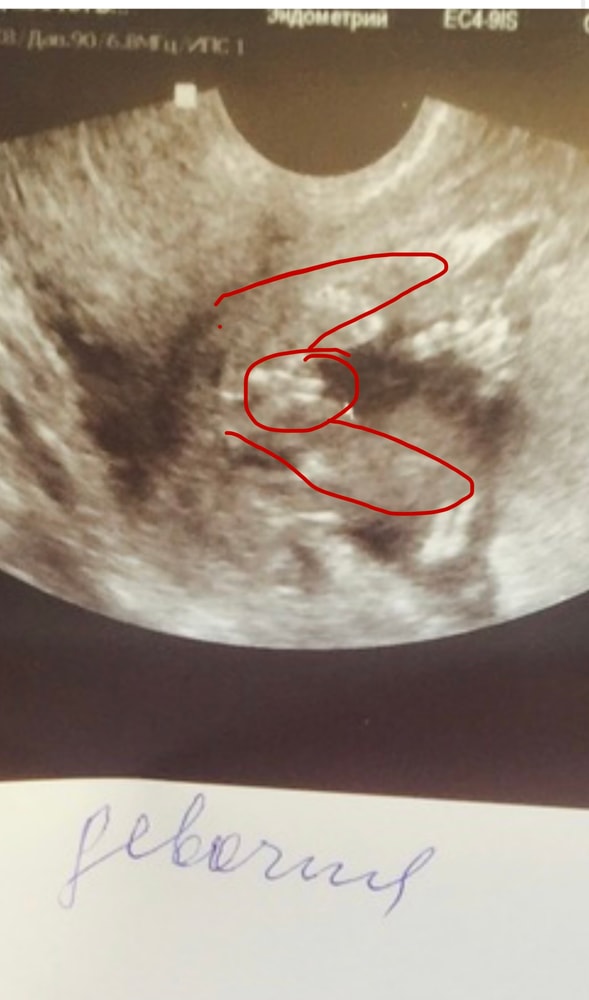

Эльза, короче я тут уже чуть ли не под лупой рассматриваю это фото😂 и вот к чему я пришла. Зеленое это всё же писюха, а красным обвела пуповину которую врач приняла за потенциальный писюн ибо мне ж сказали, что пуповина между ног Изображение Изображение

29.10.2025

Евгения, ну похоже на кофейное зернышко да. Как у девочки

Эльза, я просто перешерстила очень много фото мальчиков на этом сроке, ну там совсем не то что у нас😂 ну глянем дальше кто там всё-таки) в 11 недель по половому бугорку тут написали все девочку